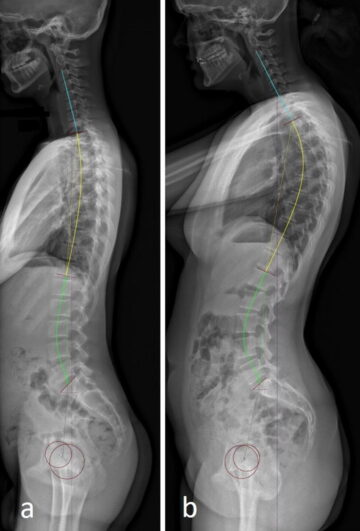

اختلال التوازن الجانبي للعمود الفقري: أسبابه، أعراضه، وطرق العلاج دليل مبسط للأهل مقدمة يعاني بعض البالغين من تشوهات العمود الفقري تؤدي إلى ميل جانبي للظهر، وهو ما يُعرف بـ اختلال التوازن الجانبي أو الانحراف

ما هو تأثير اعوجاج العمود الفقري على الظهر عند المراهقين؟ | دليلك لفهم المضاعفات يُعد اعوجاج العمود الفقري عند المراهقين من أكثر المشكلات الشائعة التي تثير قلق الأهل، خصوصًا عندما يبدأ شكل الظهر في